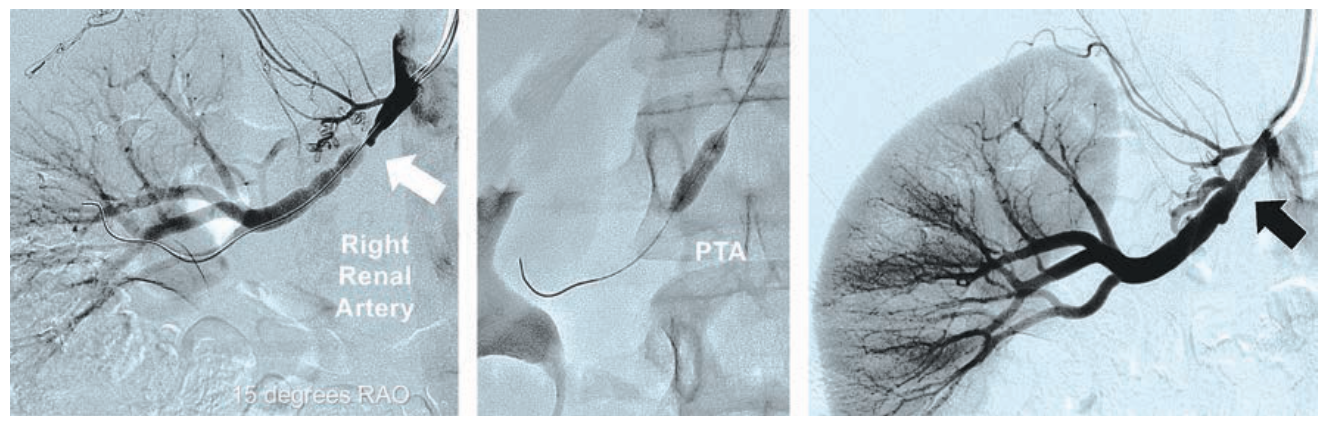

Case #6

An 18-year-old female (5 feet 2 inches, 158 cm in height) with severe hypertension requiring 3-drug therapy was found on renal artery duplex ultrasound imaging to have a right renal artery to aortic velocity ratio = 6.0. Using 5 Fr right TRA, selective renal angiography was performed with a 90 cm 5 Fr JR4 Launcher guide catheter (Medtronic), confirming severe fibromuscular dysplasia of the right renal artery (Figure 6). The lesion was crossed with a 180 cm .014-inch coronary guidewire, and PTA was performed with a noncompliant 5 mm x 15 mm coronary RX monorail balloon. Following use of a TR Band, the patient was discharged two hours later. Her hypertension subsequently resolved off all blood pressure medications.

RAO = right anterior oblique

Tips and Tricks for 5 Fr Renal Artery Intervention

In very short patients, standard 5 Fr 90 cm long coronary guiding catheters allow reach to the renal arteries, celiac, and superior mesenteric arteries from right TRA for performing PTA with coronary balloons, or for using coronary stents up to 5 mm in diameter. At present, no larger BE peripheral stents are compatible with 5 Fr guiding catheters. In taller patients, left TRA allows further reach to the abdominal aortic visceral arteries by avoiding the need to traverse tortuosity in the right subclavian artery or steeply angulated type III thoracic aortic arches. The 5 Fr Launcher coronary guide catheters can be custom ordered in 110 cm lengths (MB1 and MB2 guide catheters, Medtronic) to reach renal and mesenteric arteries using left TRA in nearly all patients, regardless of height. The 5 Fr guide sheaths and 6 Fr guiding catheters can accommodate delivery of 6- and 7-mm diameter Herculink Elite RX BE stents available in 12, 15 and 18 mm lengths, sizes generally needed for atherosclerotic disease of the renal, superior mesenteric, and celiac arteries. However, cannulation of these vessels and intervention using 5 Fr guide sheaths is technically very challenging, with most operators preferring use of 6 Fr curved guiding catheters that provide excellent coaxial support at the ostium of the downward takeoff of these arteries.